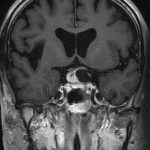

断層撮影

手術前1